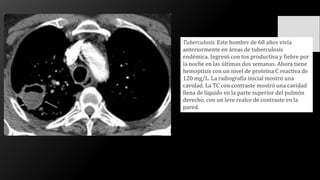

Tuberculosis. Este hombre de 68 años vivía

anteriormente en áreas de tuberculosis

endémica. Ingresó con tos productiva y fiebre por

la noche en las últimas dos semanas. Ahora tiene

hemoptisis con un nivel de proteína C reactiva de

120 mg/L. La radiografía inicial mostró una

cavidad. La TC con contraste mostró una cavidad

llena de líquido en la parte superior del pulmón

derecho, con un leve realce de contraste en la

pared.